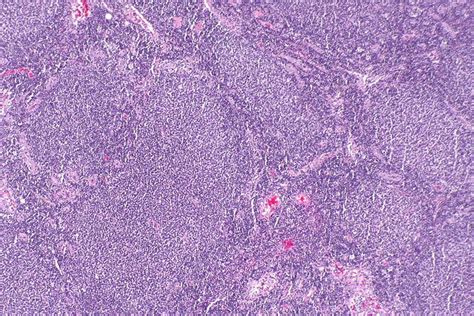

So, what exactly is follicular lymphoma ? It’s a slow-growing (indolent) type of non-Hodgkin lymphoma (NHL) that starts in the B-cells, a type of white blood cell. It gets its name from the way the cancerous cells form in the lymph nodes, creating a pattern that looks like follicles or little balls. This type of lymphoma is one of the most common types of NHL that adults are diagnosed with. It’s characterized by its generally slow progression, meaning it can often be managed effectively for many years. However, it’s important to remember that it is still a form of cancer, and while indolent, it requires careful monitoring and treatment planning. The cells involved are B-lymphocytes, and they originate in the germinal centers of lymph nodes. These germinal centers are normally where B-cells mature. In follicular lymphoma, these B-cells become abnormal and start to multiply uncontrollably within these structures. This abnormal growth can lead to the characteristic follicular pattern seen under a microscope. The disease can spread to other parts of the lymphatic system, such as the spleen, bone marrow, and sometimes even other organs, although this is less common in the early stages. The symptoms can be subtle and often include painless swelling of lymph nodes, particularly in the neck, armpits, or groin. Other general symptoms, sometimes referred to as ‘B symptoms,’ can include fever, drenching night sweats, and unexplained weight loss, though these are less common in the indolent forms and more indicative of a more aggressive presentation or transformation. Diagnosis typically involves a biopsy of an enlarged lymph node, which is then examined by a pathologist. This allows for the precise identification of the type of lymphoma and its grade (how quickly the cells are dividing). Staging is also a crucial part of the process, determining how widespread the lymphoma is throughout the body. This is usually done through imaging tests like CT scans, PET scans, and bone marrow biopsies. Understanding these diagnostic steps is key to appreciating why accurate medical coding, especially using ICD-10, is so vital for patient care, research, and billing.